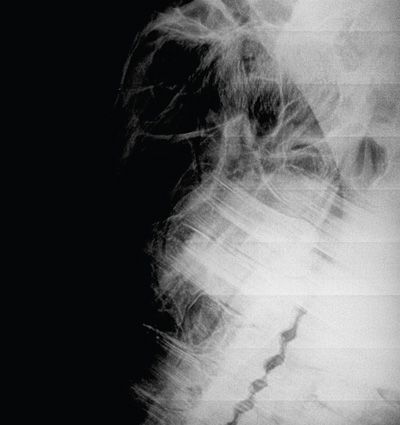

In DR systems, overexposure of radiographs often leads to saturation of the detector that reduces the ability of the pixels to differentiate grey tonal variation and can lead to a flat, poor contrast image and, in extreme cases, visualisation of the calibration mask of the detector (Figure 1). It should also be remembered that the photostimulable phosphors (PSP) of CR systems are very prone to backscatter and, if high exposures are used, will result in grey, flat images (Figure 2). The PSP plates of the CR system also need to be erased prior to any exposure and may require a double erasure if high exposure factors have been used to reduce poor contrast images and the risk of ghost images being present (Figure 3).

Figure 2. Mediolateral view of the shoulder (CR image): The radiograph of the shoulder is overexposed with poor positioning ( second shoulder superimposing) and inadequate collimation. The high exposure and large area in the primary beam have resulted in the generation of a lot of backscatter which PSP plates are very sensitive to, resulting in an image that is overly dark and grey with poor contrast.